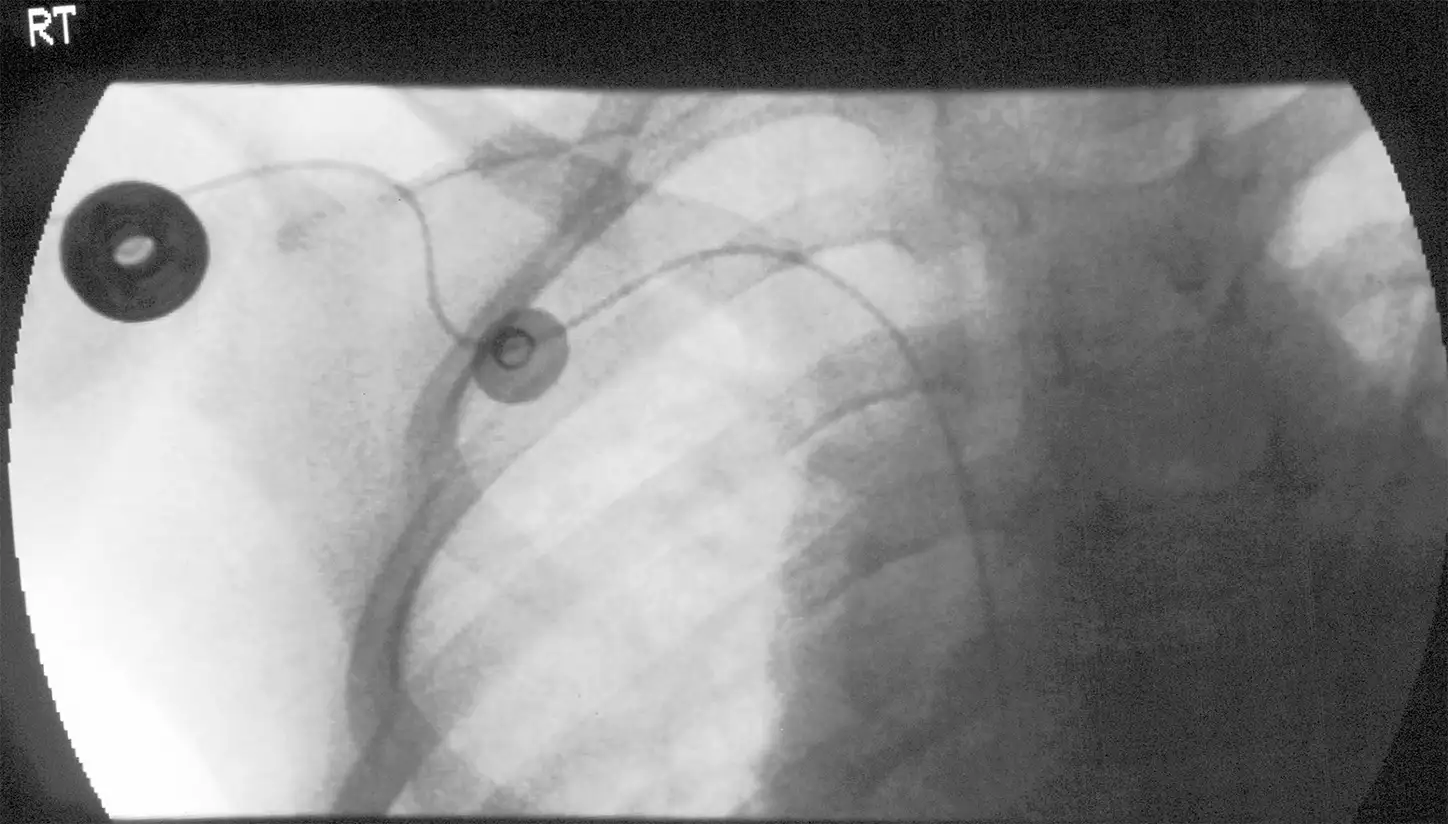

Sometimes a quick chest X-ray is required to check the placement of the line.